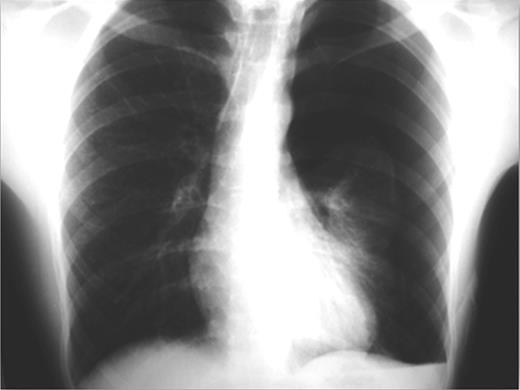

During hospitalization a chest computed tomography (CT) was performed and revealed the presence of blebs at the apices of both upper lungs (Fig. 4). After recovery the patient was referred to a tertiary center for an elective video-assisted thoracoscopic surgery intervention (VATS). Three years after, no recurrence of pneumothorax took place and the patient remains healthy.

CT image showing bilateral blebs on the apices of the upper lobes.